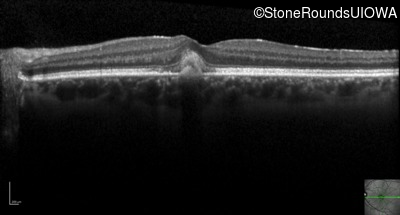

Optical Coherence Tomography - Right - 20/20 +1 sc

Exemplar / OCT Stack